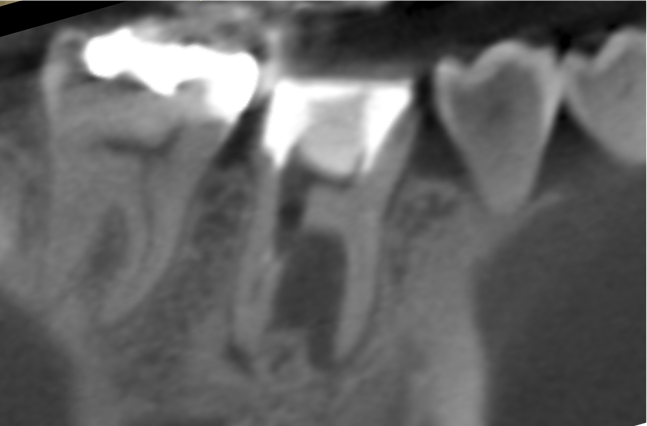

症例1:パーフォレーションリペア症例

(歯の中に大きな穴が空いてしまっているのを埋めて再生を促す治療)

歯に穴が空いていて骨に炎症がある状態 |

CTでも歯の周囲に骨がないのが分かる。 |

人為的根穿孔を起こした部分に感染を起こしており、歯周ポケットが9㎜ありました。 ラバーダム防湿とマイクロスコープを使用して丁寧に治療を行いました。 殺菌性があり歯を補強することのできるMTAという根管充填材料を使用して、歯周ポケットは2㎜に改善しました。 |